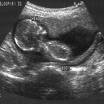

ultrasonography,  | a medical procedure that uses reflected sound to take pictures in side the body. |